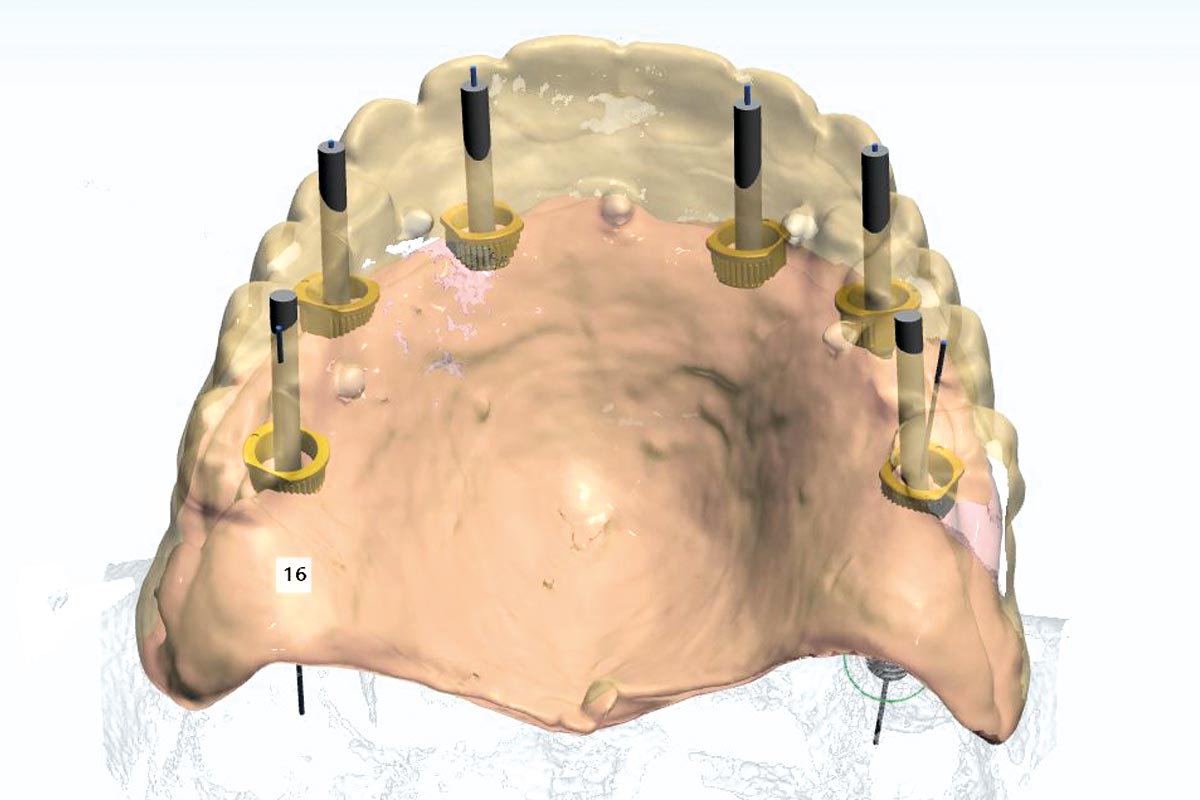

Ridge augmentation in the mandible with maxgraft® bonebuilder– Dr. R. Morger

Initial clinical situation: Free end situation in quadrant three and four